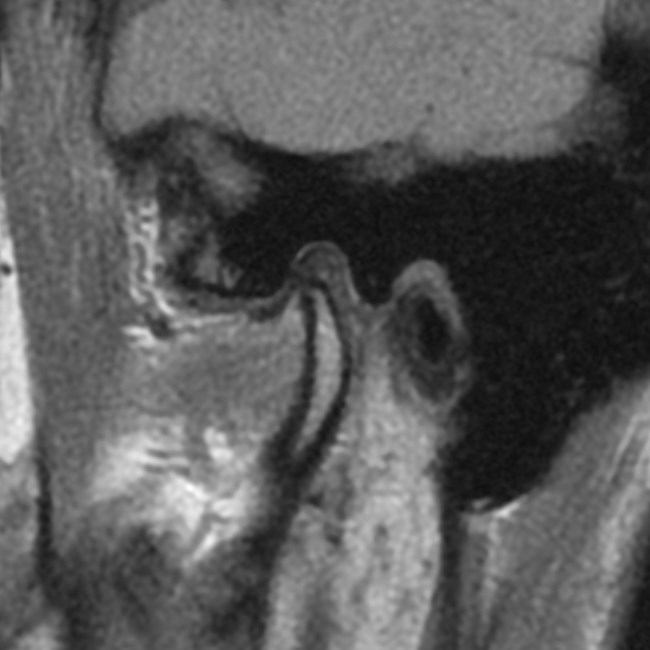

W celu oceny położenia głów żuchwy w ssż oraz wykluczenia zmian morfologicznych narządu żucia wykonano badanie tomografii stożkowej CBCT o dużym polu obrazowania, w zwarciu nawykowym. W badaniu stwierdzono asymetrię ustawienia głów żuchwy w panewkach – prawa głowa żuchwy była ustawiona bardziej dotylnie niż lewa. Z kolei lewa głowa żuchwy była ustawiona centralnie w panewce w płaszczyźnie przednio-tylnej, ale wysunięta do dołu w porównaniu z prawą głową żuchwy (ryc. 1). Na przekrojach czołowych prawa głowa żuchwy miała kształt wypukły, a lewa była spłaszczona, co może wskazywać na zmiany zwyrodnieniowe (ryc. 2). W badaniu CBCT nie stwierdzono obecności zmian zapalnych okołowierzchołkowych, które mogłyby być przyczyną dolegliwości bólowych, jak też zmian zapalnych zatok obocznych nosa.

Ryc. 1. Przekroje strzałkowe ssż w tomografii stożkowej ukazują asymetrię ustawienia głów żuchwy w panewkach – prawa głowa żuchwy ustawiona bardziej dotylnie niż lewa. Lewa głowa żuchwy jest ustawiona centralnie w panewce w płaszczyźnie przednio-tylnej, ale wysunięta do dołu w porównaniu z prawą głową żuchwy.